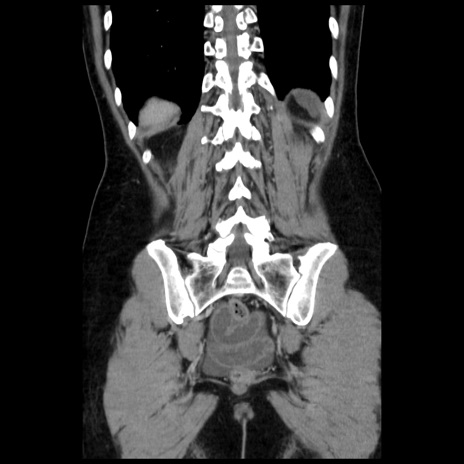

症例10(冠状断像)

【症例】 50歳代女性

【主訴】 腹痛

【現病歴】前日生レバーを食べた。今朝に排便あり。 昼前に突然発症の腹痛を生じ、当院救急外来を受診した。

【既往歴】 子宮筋腫にてで子宮全摘後

【身体所見】 意識清明、腹部:平坦、軟、下腹部やや左を中心に圧痛・反跳痛あり、筋性防御あり

【データ】WBC 7800、CRP 0.07